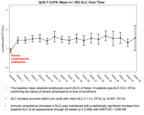

- Baseline mean absolute lymphocyte count (ALC) among these 14 patients was 0.9 x 103/uL, confirming severe lymphopenia at enrollment

- ALC increased within one treatment cycle, with mean ALC rising to ≥ 1.4 x 103/uL (p <0.001, N=14)

- Immune competence (as measured by ALC) was maintained, with statistically significant increases from baseline observed at all assessments through 20 weeks (p ≤ 0.026) with ANKTIVA® + CAR-NK

Immune competence and lymphocyte recovery

At study entry, patients demonstrated immune compromise consistent with prior standard of care, including radiation and alkylating chemotherapy. The baseline mean absolute lymphocyte count (ALC) was approximately 900 cells per µL, consistent with lymphopenia commonly observed after prior therapy in recurrent GBM. See figure 3.

“These Phase 2 data reflect outcomes in a second- and third-line glioblastoma population where immune collapse after standard therapy is common and options are limited. With 19 of 23 enrolled patients alive and median overall survival not yet reached, the survival profile warrants continued follow up,” said Patrick Soon Shiong, M.D., Founder, Executive Chairman and Global Chief Scientific and Medical Officer of ImmunityBio. “It has been extensively reported that patients with glioblastoma and lymphopenia have a significant decreased survival. Current standards of care, including radiation and chemotherapy (temozolomide), are potent drivers of lymphocyte depletion. The patients that entered this study all suffered profound lymphopenia, reflected by a baseline mean ALC of approximately 900, consistent with prior radiation and chemotherapy exposure. On treatment, we observed recovery and maintenance of lymphocyte counts without chemotherapy. Notably, within this broader clinical and compassionate use experience, we have also observed a near complete response with survival extending beyond twelve months from the time of documented disease progression, an outcome rarely seen in recurrent glioblastoma.”